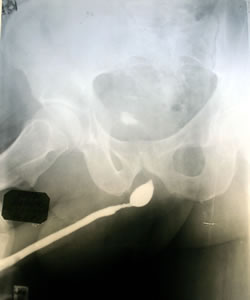

Методика и показания к восходящей ретроградной уретрографии